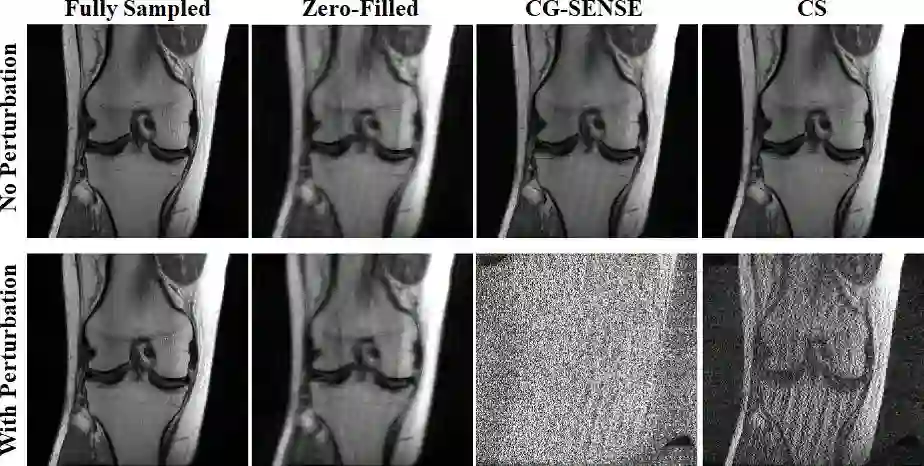

Although deep learning (DL) has received much attention in accelerated MRI, recent studies suggest small perturbations may lead to instabilities in DL-based reconstructions, leading to concern for their clinical application. However, these works focus on single-coil acquisitions, which is not practical. We investigate instabilities caused by small adversarial attacks for multi-coil acquisitions. Our results suggest that, parallel imaging and multi-coil CS exhibit considerable instabilities against small adversarial perturbations.